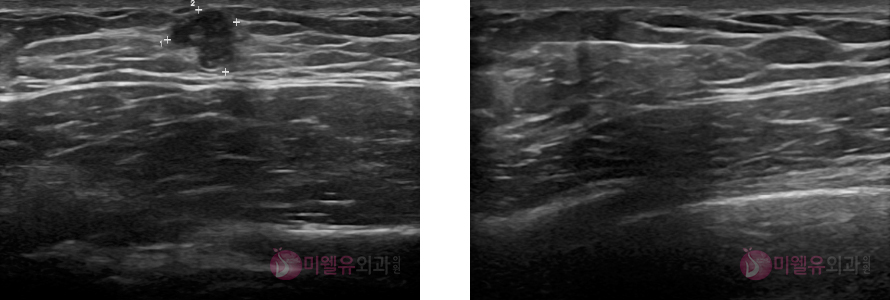

42세 여자분으로 이전에 오른쪽에 유방에 혹이 있어서 추적관찰위해 내원하셨던 분입니다.

그런데 진찰상으로는 왼쪽 유방에 단단한 멍울이 잡혔고, 환자 본인은 몰랐던 멍울이었습니다.

초음파상 유방암이 의심이 되어 조직검사 시행했으며 검사 결과 유방암으로 진단된 분입니다.

40대는 유방암이 가장 호발하는 시기입니다.

이때는 이전에 괜찮았다 하더라도 다른 부위에 얼마든지 암이 발생할 수 있으므로 혹이 있을

경우6개월마다 정기 검사를 받는 것이 중요하겠습니다.